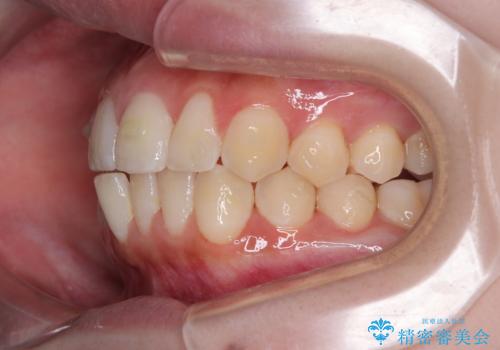

- 今回は「下の前歯のデコボコを治したい」と来院された患者様の症例をご紹介します。

診察してみると、下の前歯が並ぶためのスペースが足りないことが、歯並びがデコボコしている原因でした。

そこで今回は、以下の2つの方法を組み合わせて治療を行いました:

下の前歯の歯と歯の間をわずかに削ってスペースを作る(IPR)

奥歯を後ろに動かして、前歯が並ぶためのスペースを確保する

この計画により、デコボコだった下の前歯はしっかりと並び、わずか1年で治療を終えることができました

見た目が気にならないマウスピース矯正だったこともあり、患者様にも大変ご満足いただけました。